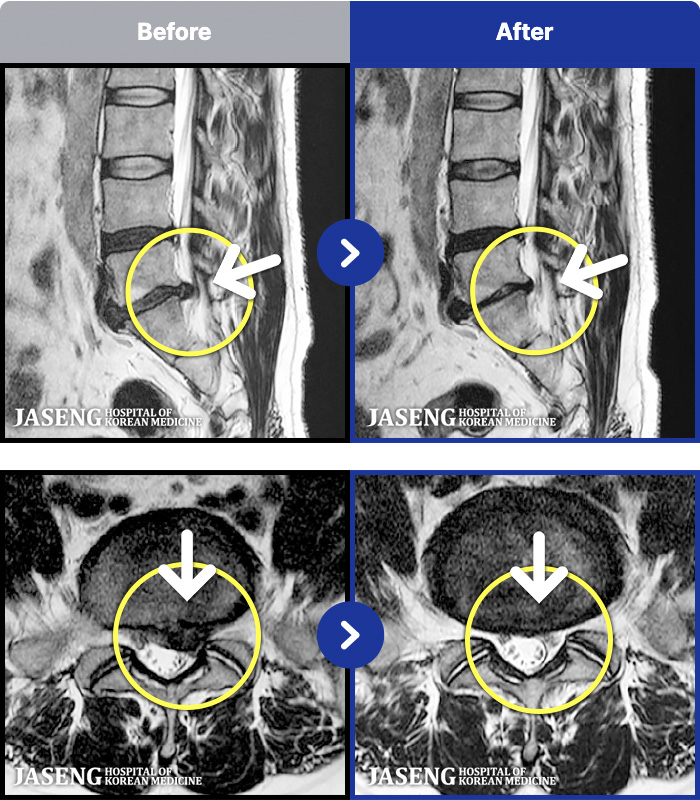

- MRI ġ

MRI ġ

1,237 MRI ũ ʸ Ȯϼ.